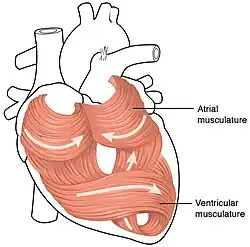

A camada intermédia da parede do coração é o miocárdio, que é o músculo cardíaco. Trata-se de uma camada de tecido muscular estriado envolvida por uma estrutura de colagénio. O padrão do músculo cardíaco é intrincado e complexo, de modo a permitir ao coração bombear sangue com maior eficácia. As células musculares fazem uma espiral à volta das cavidades do coração, em que os músculos exteriores formam um 8 à volta das aurículas e das bases dos grandes vasos, e os músculos interiores formam um 8 à volta dos dois ventrículos em direção ao ápice.[7]

Estrutura do músculo cardíaco

Existem dois tipos de células no músculo cardíaco: os cardiomiócitos, células musculares com a capacidade de se contraírem facilmente, e as células marca-passo do sistema condutor. As células musculares constituem a maioria (99%) das células nas aurículas e nos ventrículos. Estas células contrácteis estão ligadas por discos intercalares que possibilitam uma resposta rápida aos impulsos do potencial de ação cardíaco das células marca-passo. Os discos intercalares fazem com que as células atuem como sincícios e possibilitam as contrações que bombeiam o sangue através do coração e para as principais artérias do corpo.[7] As células marca-passo correspondem a 1% das células e constituem o sistema de condução elétrica do coração. São geralmente muito menores que as células contractéis e possuem poucas miofibrilhas, o que limita a sua capacidade de contração. Em muitos aspetos, a sua função é semelhante à dos neurónios.[7] O músculo cardíaco possui auto-ritmicidade, a capacidade de iniciar um potencial de ação cardíaco a um ritmo fixo, propagando rapidamente o impulso elétrico de modo a contrair todo o coração.[7]